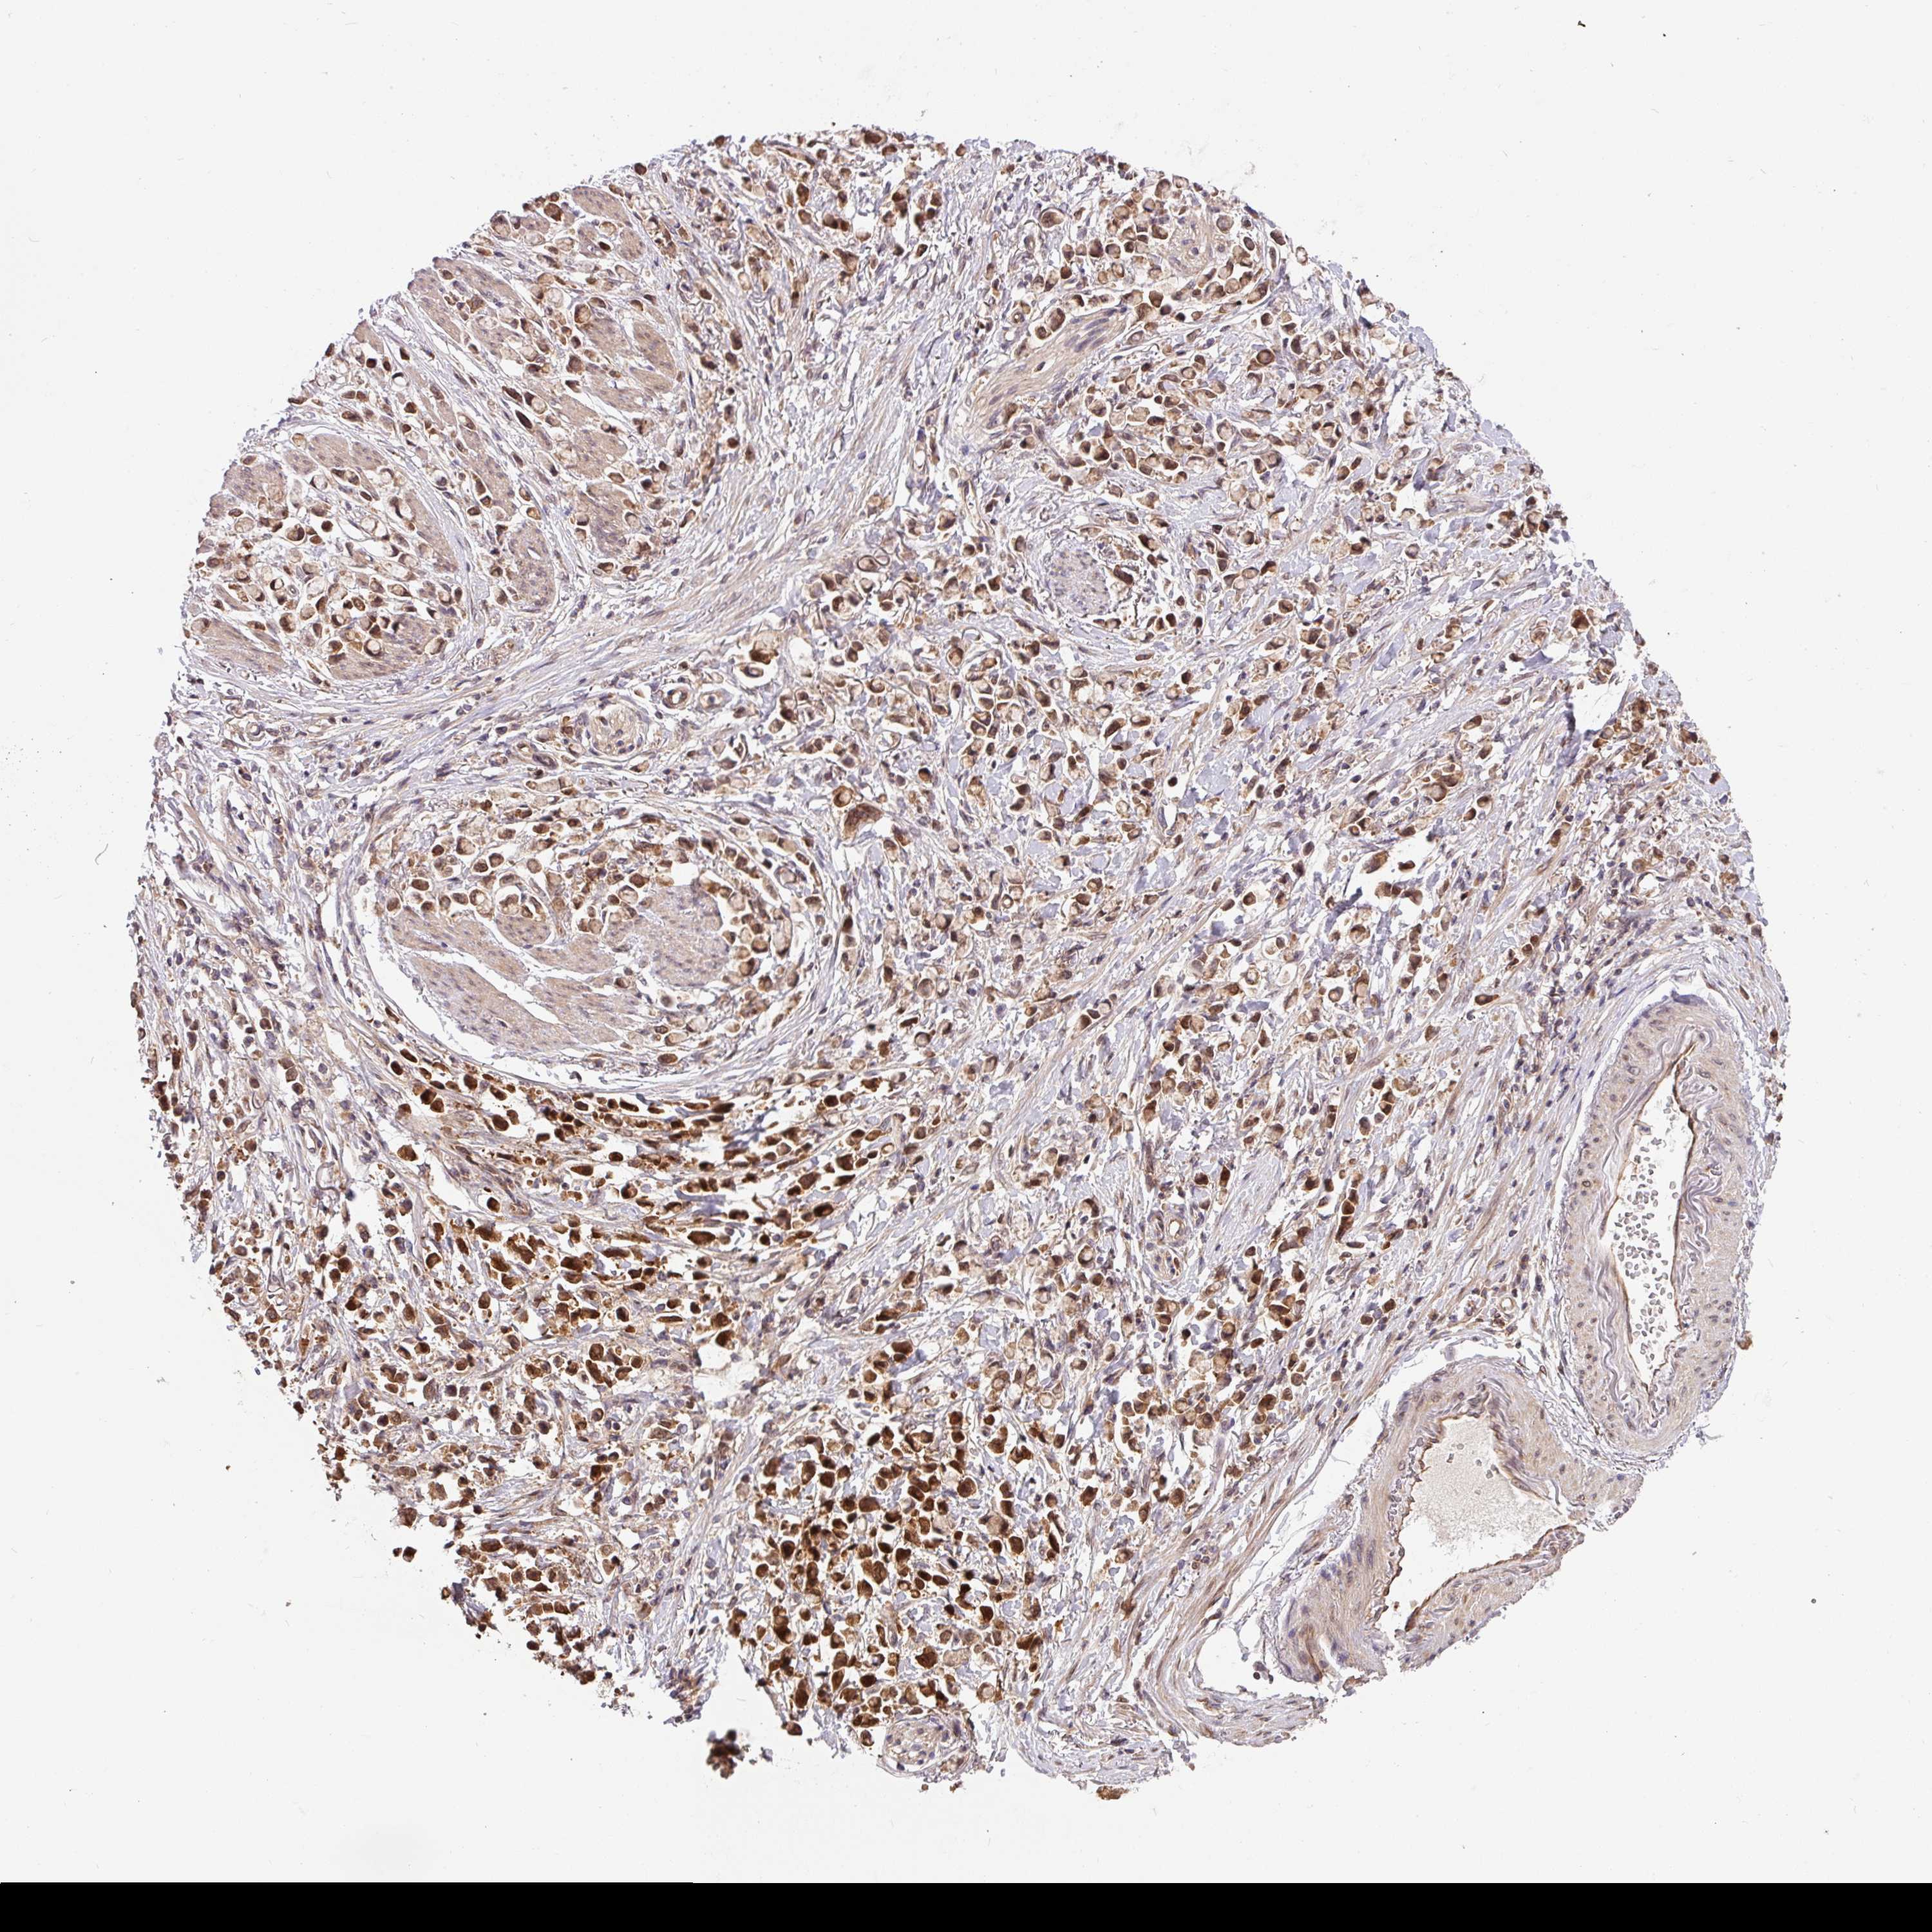

STOMACH CANCER - Protein expressioni

A mouse-over function shows sample information and annotation data. Click on an image to view it in a full screen mode. Samples can be filtered based on level of antibody staining by selecting one or several of the following categories: high, medium, low and not detected. The assay and annotation is described here.

Note that samples used for immunohistochemistry by the Human Protein Atlas do not correspond to samples in the TCGA dataset.

Antibody stainingi

Antibody staining in the annotated cell types in the current human tissue is reported as not detected, low, medium, or high, based on conventional immunohistochemistry profiling in selected tissues. This score is based on the combination of the staining intensity and fraction of stained cells.

Each image is clickable and will lead to virtual microscopy that enables deeper exploration of all samples and also displays staining intensity scores, fraction scores and subcellular localization as well as patient and tissue information for each sample.

Antibody HPA049911

Antibody CAB010161

Staining

High

Medium

Low

Not detected

Intensity

Strong

Moderate

Weak

Negative

Quantity

>75%

75%-25%

<25%

None

Location

Nuclear

Cytoplasmic/membranous

Cytoplasmic/membranous,nuclear

Adenocarcinoma, NOS